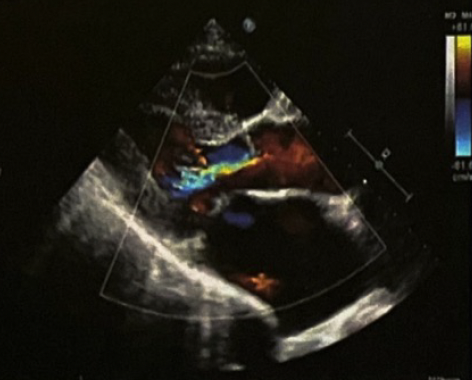

◆超声心动图:左心房、右心房扩大(LA5.1cm,RA4.6cm);升主动脉增宽;主动脉瓣中度反流;二尖瓣中度反流;三尖瓣中度反流;室间隔增厚;心律失常(图2)。

.png)

图2. 超声心动图